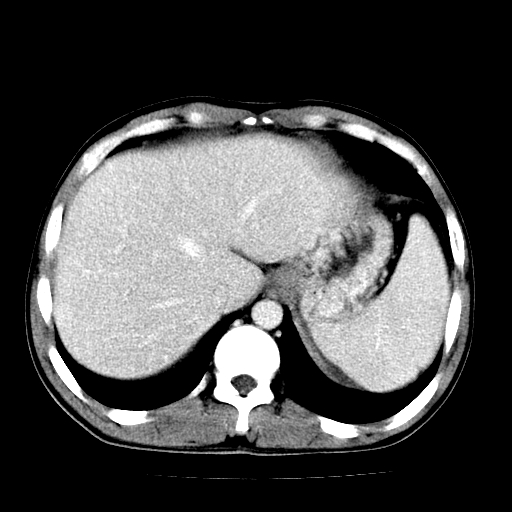

以下是引用天南地北在2007-4-30 13:36:00的发言:[br]支持慢性胰腺炎伴有假性囊肿

以下是引用andymaomao在2007-4-30 14:28:00的发言:[br]支持:1.慢性胰腺炎并假性囊肿形成可能;[br] 2.左肾形态稍增大,旋转不良。